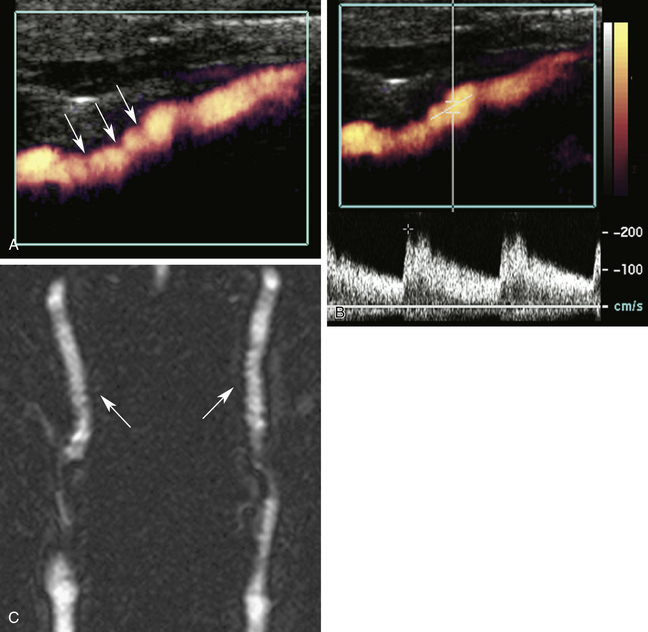

РИСУНОК 10-9. Каротидно-фибромышечная дисплазия. А. На этом энергетическом допплеровском изображении виден ряд выступов ( стрелок ) вдоль просвета внутренней сонной артерии, характерных для фибромускулярной дисплазии. Б. Спектральная допплерография показывает умеренное нарушение потока и повышение скорости потока (около 200 см/сек). C. Магнитно-резонансная ангиография демонстрирует классический вид гребней на обеих внутренних сонных артериях ( стрелки ).